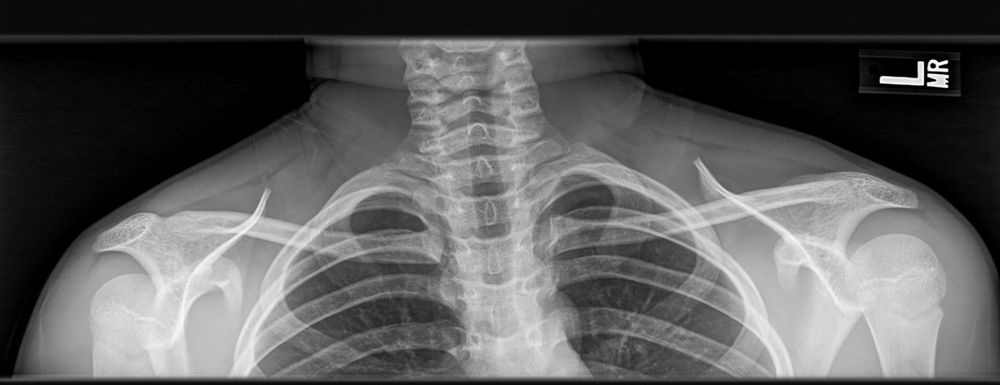

XR here:

November 17, 2025 at 9:04 PM

16y/o M presents after falling on R shoulder during a 🏈game. Multiple players fell on him. Complains of mid chest pain& can't fully flex @ the shoulder. Voice is a bit hoarse. What's your management?

1️⃣ <a href="https://poll.blue/p/KWjeET/1" class="hover:underline text-blue-600 dark:text-sky-400 no-card-link" target="_blank" rel="noopener" data-link="bsky">Motrin & d/c

2️⃣ <a href="https://poll.blue/p/KWjeET/2" class="hover:underline text-blue-600 dark:text-sky-400 no-card-link" target="_blank" rel="noopener" data-link="bsky">Sling & PT

3️⃣ <a href="https://poll.blue/p/KWjeET/3" class="hover:underline text-blue-600 dark:text-sky-400 no-card-link" target="_blank" rel="noopener" data-link="bsky">Needle decompression

4️⃣ <a href="https://poll.blue/p/KWjeET/4" class="hover:underline text-blue-600 dark:text-sky-400 no-card-link" target="_blank" rel="noopener" data-link="bsky">CT chest